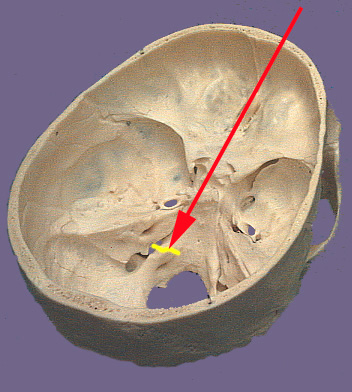

Cranium CN IX

The glossopharyngeal nerve as its name suggests is related to the tongue and the pharynx. The ninth cranial nerve exits the brain stem as a the most rostral of a series of nerve rootlets that protrude between the olive and inferior cerebellar peduncle. These nerve rootlets come together to form the ninth cranial nerve and leave the skull through the jugular foramen. The tympanic nerve is a branch that is occurs prior to exit the skull. The visceromotor or parasympathetic part of the ninth nerve originate in the inferior salivatory nucleus. Nerve fibers from this nucleus join the other components of the ninth nerve during their exit from the brain stem. They branch in the cranium as the tympanic nerve. The tympanic nerve exits the jugular foramen and passes by the inferior glossopharyngeal ganglion. It re-enters the skull through the inferior tympanic canaliculus and reaches the tympanic cavity where it forms a plexus in the middle ear cavity. The nerve travels from this plexus through a canal and out into the middle cranial fossa adjacent to the exit of the greater petrosal nerve. It is here the nerve becomes the lesser petrosal nerve. The lesser petrosal nerve exits the cranium via the foramen ovali and synapses in the otic ganglion. The otic ganglion provides nerve fibers that innervate and control the parotid gland, an important salivary gland. The branchial motor component supplies the stylopharyngeas muscle which elevates the pharynx during swallowing and talking. In the jugular foramen are two sensory ganglion connected to the ninth cranial nerve: the superior and inferior glossopharyngeal ganglia. General sensory components from the skin of the external ear, inner surface of the tympanic membrane, posterior one-third of the tongue and the upper pharynx join either the superior or inferior glossopharyngeal ganglia. The ganglia send central processes into the brain stem which terminate in the caudal part of the spinal trigeminal nucleus. Visceral sensory nerve fibers originate from the carotid body (oxygen tension measurement) and carotid sinus (blood pressure changes). The visceral sensory nerve components connect to the inferior glossopharngeal ganglion. The central process extend from the ganglion and enter the brain stem to terminate in the nucleus solitarius. Taste from the posterior one-third of the tongue travels via nerve fibers that enter the inferior glossopharnygeal ganglion. The central process that carry this special sense travel through the jugular foramen and enter the brain stem. They terminate in the rostral part of the nucleus solitarius (gustatory nucleus).